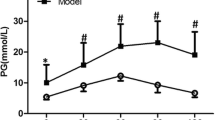

Human atrial myocardial functional response to β-adrenergic stimulation

As impaired diastolic function limits cardiac performance during exercise[11], we also evaluated whether the impaired relaxation observed in the diabetic right atrial myocardium might be further compromised during a physiological challenge. Therefore, the human right atrial cardiac muscles were also exposed to β-adrenergic stimulation using incrementing doses of dobutamine (10-7 to 10-5 M). As expected, this resulted in an increase in the amplitude of contraction (Fdev, Figure 3A), speed of contraction (+dF/dtmax, Figure 3B), speed of early relaxation (-dF/dtmin, Figure 3C) and of late relaxation (Tau, Figure 3D) in muscles from non-DM patients. Strikingly, the β-adrenergic stimulation-induced increase in contractility (Fdev and + dF/dtmax, Figure 3A and B) and acceleration of relaxation (-dF/dtmin and Tau, Figure 3C and D) were absent in muscles from DM patients. Using western blot analysis we assessed whether the impaired inotropic and lusitropic β-adrenergic responsiveness in diabetic myocardium was related to reduced β1-adrenoreceptor content. However, as shown in Figure 3F the expression levels of the β1-adrenoreceptor were not different between cardiac tissue samples from the non-DM and DM patients (2.3 ± 0.3 vs. 1.9 ± 0.2 non-DM vs. DM, p = 0.22).

Myocardial function during β-adrenergic stimulation. In response to incrementing doses of β-adrenergic agonist dobutamine (10-7 to 10-5 M) right atrial cardiac muscles from non-diabetic patients (non-DM, closed circles, n = 8) showed an increase in amplitude of contraction (Fdev, A), and speed of contraction (+dF/dtmax, B); and a faster speed of early relaxation (-dF/dtmin, C) and late relaxation (Tau, D). Strikingly, both the increase in the contractile parameters (Fdev and + dF/dtmax) and the hastening of the relaxation parameters (-dF/dtmin and Tau) were absent in the cardiac muscles from the diabetic patients (DM, open circles, n = 6). E. Western blotting was performed with human cardiac tissue samples from non-diabetic (non-DM) and diabetic (DM) patients probed for β1–adrenoceptor (β1-AR) and β-actin. In representative blot β1–AR was detected just below 50 kDa and β-actin above 37 kDa as loading control. F. Western blot analysis showed similar protein expression for β1–adrenoceptor. For all functional parameters two-way ANOVA Bonferroni’s posthoc: dose effect, * = p < 0.05 and DM effect, # = p < 0.05). For protein analysis data obtained from four replica experiments, non-DM (n = 10) and DM (n = 9) patients, unpaired t-test. Data are mean ± SEM.

Impaired relaxation during physiological challenge

Although contractile function at rest was not altered by diabetes, the relaxation of the right atrial diabetic muscles was impaired over the entire range of myocardial stretch, and both the inotropic and lusitropic responses to β-adrenergic stimulation were completely absent in cardiac muscles from DM patients. A reduced but still responsive myocardium to β-adrenergic stimulation has been observed in many diabetic animal models[33, 34] and has been related to reduced expression levels of β1-adrenoreceptors[35]. Surprisingly, cardiac muscles from our cohort of diabetic patients failed to respond to the β-adrenergic stimulation, even at very high (10-5 M) concentrations, which would indicate a lack of contractile reserve even in these patients with normal resting contractile function. In addition, our new data emphasizes that caution should be taken with translating animal data directly to the human situation. It would be easy to attribute this to the use of β-adrenoceptor blocking agents, however almost all patients, both the diabetic and the non-diabetic, were on β-blocker treatment (Table 1). Secondly, although the hemodynamic responses to dobutamine are reduced in diabetic patients[36] they normally still do respond. Consequently the non-responsiveness to β-adrenergic stimulation in the isolated right atrial cardiac muscles in our study should reside within the myocardium. Thirdly, although a reduced expression of β1-adrenoreceptors has been reported in myocardial tissue from diabetic patients undergoing CABG in the absence of β-blockers[37], to the best of our knowledge expression of β1-adrenoreceptors has never been reported in human myocardial tissue from diabetic patients with preserved EF. Interestingly, we did not observe a statistically significant reduction in β1-adrenoreceptors expression levels (Figure 3F) in the cardiac tissue from our diabetic cohort. Therefore, we suggest that the reduced β-adrenergic inotropic and lusitropic responses in the diabetic myocardium from patients with preserved EF are related to alterations in downstream β-adrenergic signaling pathways. Phosphorylation of PLB is an important downstream target of β-adrenergic signaling and we observed a markedly reduced PLB protein expression in the diabetic myocardium. Indirectly this implies there is less PLB to be phosphorylated and therefore this could be the reason for the reduced β-adrenergic inotropic and lusitropic responses in the diabetic myocardium from patients with preserved EF. Alternatively, Daniels et al. suggested that reduced β-adrenergic responsiveness in diabetes is related to metabolic changes leading to impaired energy conversion, which becomes apparent during physiological challenge[34]. Additionally, it was recently shown that although exercise limitations were similar between patients with reduced and preserved EF, significant differences occurred in their exercise-induced changes in systolic and diastolic properties, again reflecting their different underlying pathologies[38].